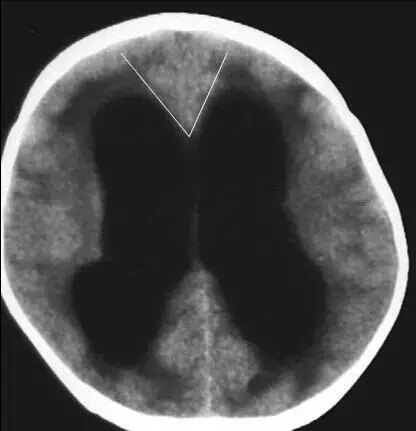

第一招:额角角度

脑萎缩~钝角

脑积水~锐角